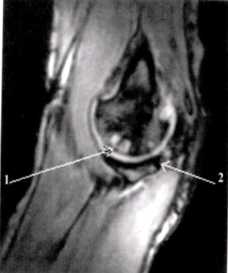

МРТ картина синовита, стрелками указаны участки отека костной ткани локтевого отростка

Синдром поражения суставов

Большинство изменений локтевого сустава сопровождается симптомами сопутствующего экссудативного синовита; его выраженность зависит от тяжести травм. На МРТ выявляется суставной выпот. Кроме того, иногда определяется отек костного мозга в субхондральных отделах эпифизов костей, отек периартикулярных мягких тканей.

МР-признаки незначительного синовита локтевого сустава; отечность мягких тканей (трехглавой мышцы плеча и глубокого сгибателя пальцев) нижней поверхности сустава; нельзя исключить минимальные проявления посттравматического липоартрита.

МР-картина структурных изменений в виде фокуса и очага отека трабекулярной костной ткани локтевого отростка локтевой кости и головки лучевой кости. Нерезко выраженный синовит.

МР-картина частичного разрыва сухожилия двуглавой мышцы плеча. Признаки частичного повреждения дистальных отделов сухожилия плечевой мышцы, в большей степени в месте прикрепления. Начальные проявления артроза локтевого сустава. Синовит. Отек медиальных отделов периартикулярных мягких тканей.